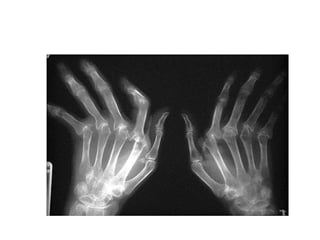

• X-rays: Juxta-articular osteopenia,

bone erosion with narrowing of joint

space from loss of articular cartilage.

• Swollen, painful,morning stiffness. • Disease may be slow or rapid & fluctuates over period of years with periods of partial or complete remission. • Maximum damage occurs during the 1st 4 -5 yrs. • X-rays: Juxta-articular osteopenia, bone erosion with narrowing of joint space from loss of articular cartilage.

CHARACTERISTIC GROSS DEFORMITIES: • Radialdeviation of wrist. • Ulnar deviation of fingers. • Flexion-hyperextension of fingers (swan neck). • Bakers cyst (large synovial cysts) in post knee due to ↑ intraarticular pressure.